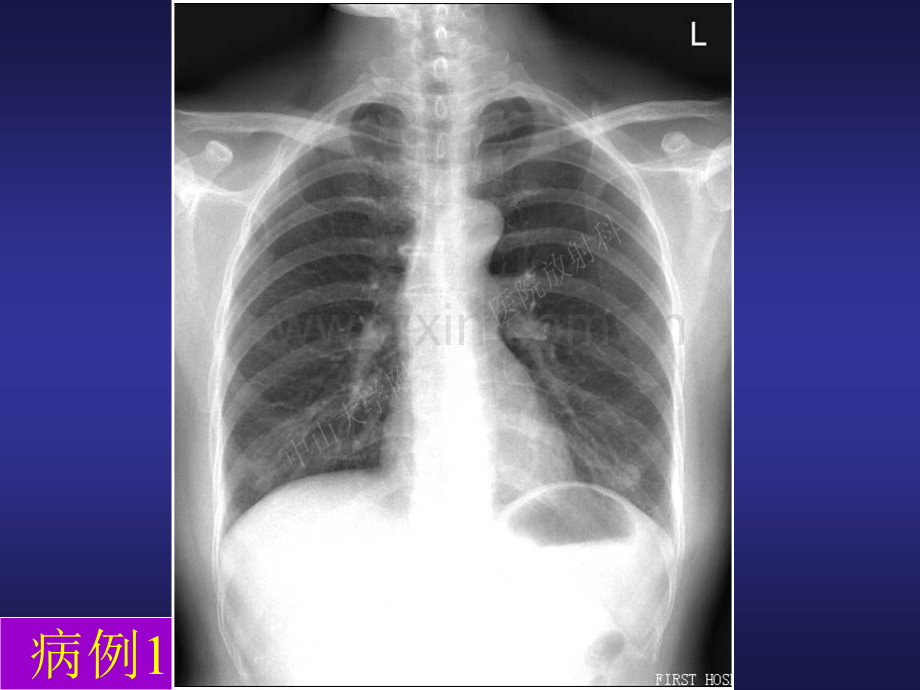

呼吸系统呼吸系统X X线解剖、线解剖、正常表现、基本病正常表现、基本病征征病例1问题s该患者的胸片图像质量是否合格,合格正位胸片的标准如何?s该患者的胸片有无异常,如何鉴别是否正常结构。s阅片的基本原则(顺序、对比、解剖、病理)病例2:请根据你的知识指出该胸片中的正常结构有无异常征象,如有请指出病例2:请指出该侧位胸片中的正常结构有无异常征象,如有请指出图示的图片是什么影像学检查手段获得,理由?两张图片有什么不同,理由?图示两幅图片有无区别,区别何在?你对此有何体 会?以下几幅图提示了多层螺旋 CT成像中的哪一个重要特性,如何理解和应用这个特点?图中所示是否为病变?能指出斜裂和水平裂的位置吗?能指出斜裂和水平裂的位置吗?有何临床意义?左右斜裂在胸片上有何异同点?知道正位胸片上肺叶大致分界吗?问题s前面每幅幻灯上的两张CT片是用什么窗观察,显示的结构有何不同?s叶间胸膜在两张图片上的显示有无不同?解释原因?能用CT定位肺叶吗?用CT图像进行肺叶定位能指出几个典型的次级肺小叶结构吗?显示小叶间隔有何临床意义?食管食管气管气管侧位胸片上纵隔是如何分区的?临床意义如何?纵纵隔隔侧侧位位箭头所示为什么结构?问题s幻灯所示CT片是什么窗技术,观察方向如何?s你能指出其中的多少正常结构?侧位胸片上如何区分左膈和右膈看图说话看图说话看图说话看图说话看图说话看图说话右上叶不张右中叶不张右下叶不张左上叶不张仔细观察这几张图片后看图说话看图说话看图说话看图说话看图说话看图说话看图说话问题s在正位胸片上右肺上叶和左肺上叶不张的区别何在,产生这种区别的解剖学基础是什么?s你觉得哪一个肺叶不张在正位胸片中较难观察,理由是什么?s胸片出现肺叶不张时为什么要进一步检查。看图说话看图说话看图说话看图说话看图说话问题sX线胸片上肺门异常包括那些s出现肺门异常时如何选择检查手段问题s你觉得影像学检查在临床诊疗工作中扮演着什么角色s你觉得学好影像学需要特别注重那些基础知识s你会来从事影像学工作吗s熟悉正常s明辨异常s结合临床s综合分析影像诊断基本原则呼吸系统基本病征(36)、肺结核复习回答问题s产生肺实变的主要疾病种类有哪些,每一种疾病产生实变的病理基础如何?s实变的表现形式主要有哪几种,解释其解剖学基础1、描述上面两个病例的胸片征象2、给两个病例的病变定位并说明理由1、描述上面胸片所示病变的征象2、上面胸片所示的病变是什么性质的病变,解释产生上述征象的病理学基础和解剖学基础1、描述CT片所示病变的征象2、片中所示的病变是什么性质的病变,解释产生上述征象的病理学基础和解剖学基础图中所示为什么性质的病变,说明理由1、指出图示CT片所用的窗技术;2、观察肺部病变形态和测量病变密度应选择什么窗技术,说明理由图中所示为什么性质的病变,说明理由图中所示为什么性质的病变,说明理由描述图中所示病变征象,并说明病变的性质描述图中所示病变征象,并说明病变的性质1、描述图中所示病变征象,并说明病变的性质;2、与肺不张如何鉴别1、描述图中所示病变征象,并说明病变的性质;2、与肺不张如何鉴别1、描述图中所示病变征象,并说明病变的性质;1、描述图中所示病变征象,并说明病变的性质只要见到病灶内部钙化则基本可以诊断为良性,对吗,说明理由浏览以下几张幻灯图片后回答问题s肺内那些病变可以表现为结节或肿块s对这些病变如何进行鉴别阅读以下图片后回答问题s以下图片中那些是良性病变,那些是恶性病变s阐述良性和恶性结节或肿块的鉴别描述图示病变的征象,上述征象的产生可能是什么病变所致并解释之描述图示病变的征象,上述征象的产生可能是什么病变所致并解释之浏览以下幻灯片后回答问题s这些病变共有的特点是什么s肺内那些病变可以有如此表现s对可能产生这种征象的病变如何进行鉴别描述图示病变的征象,上述征象的产生可能是什么病变所致并解释之1描述图示病变的征象,上述征象的产生可能是什么病变所致并解释之;2与气胸如何鉴别1描述图示病变的征象,上述征象的产生可能是什么病变所致并解释之;2与转移瘤如何鉴别1描述图示病变的征象,上述征象的产生可能是什么病变所致并解释之浏览以下幻灯后回答问题s产生下图所见征象的原因是什么s如何与肺不张和肺实变鉴别1描述图示病变的征象,上述征象的产生可能是什么病变所致并解释之1描述图示病变的征象,上述征象的产生可能是什么病变所致并解释之卧位立位图中所示为什么病变,说明理由看图说话看图说话看图说话看图说话看图说话看图说话放大图示为什么征象,如何与胸腔积液鉴别看图说话看图说话看图说话这是发生在什么位置的病变,鉴别诊断包括那些,你考虑为良性还是恶性,以什么病变的可能性较大62岁女性看图说话看图说话看图说话s浏览以下两张幻灯片后比较其不同左上肺继发性结核(渗出为主)左上肺野散在多发斑片状阴影,大部分边缘模糊双上肺继发性结核(渗出为主)深入成就深度 广度决定高度 理念决定方向